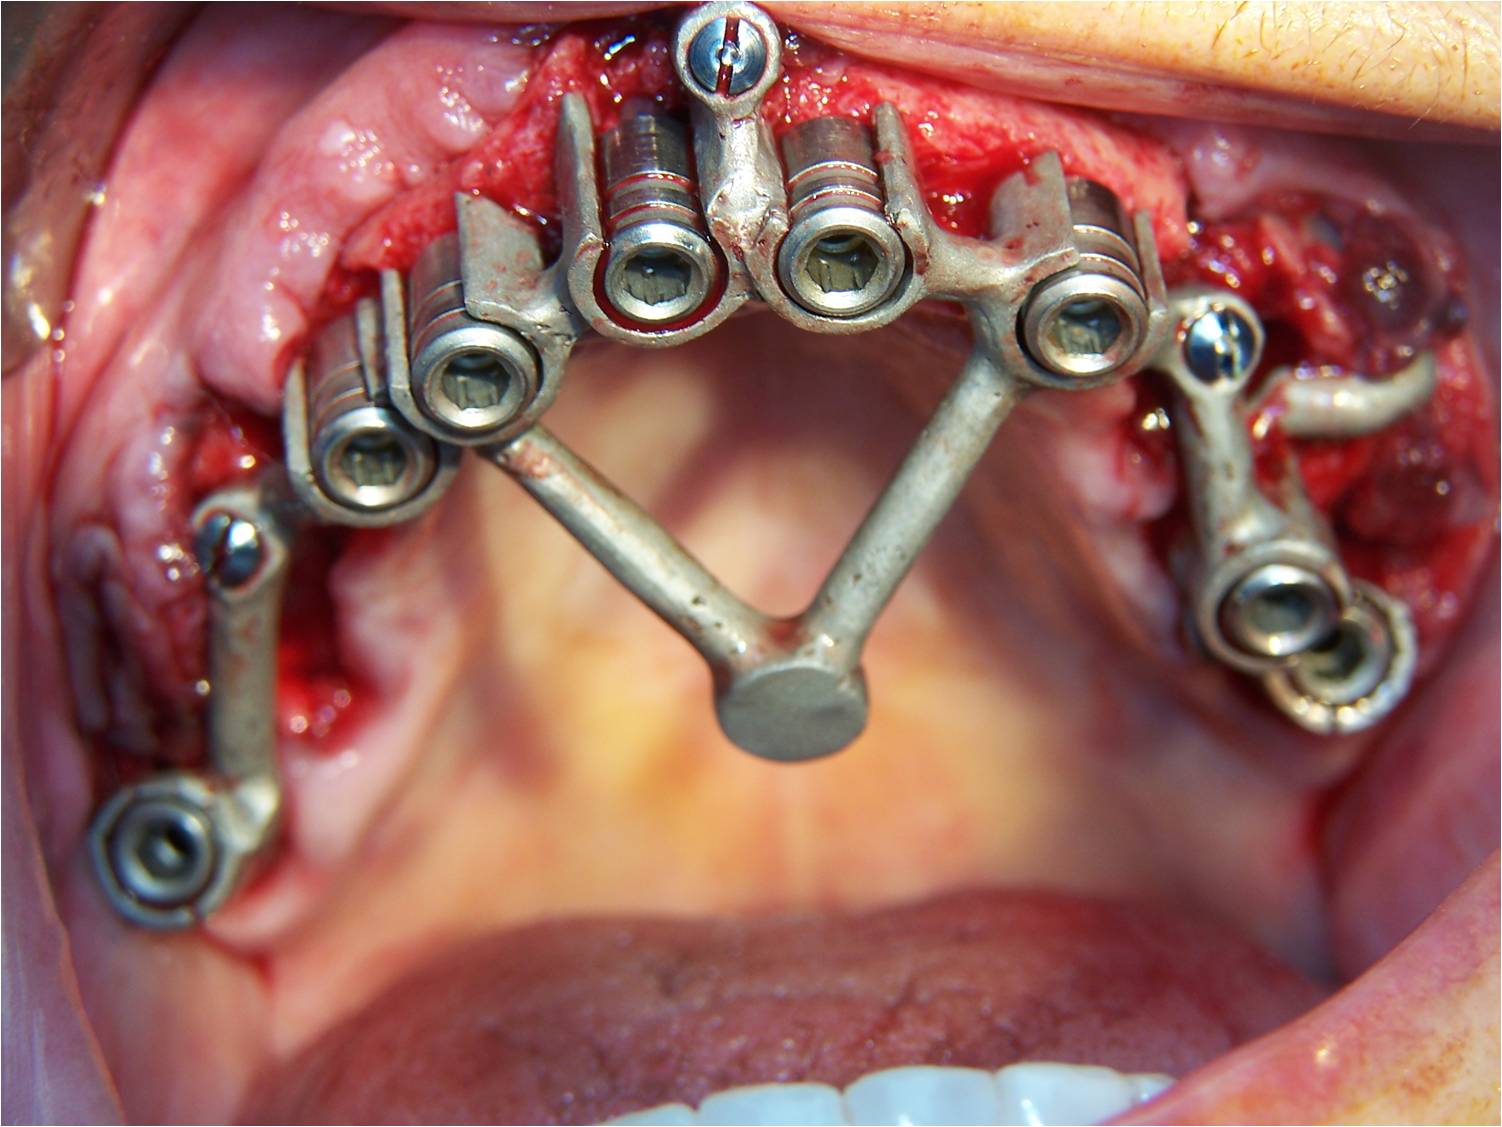

Ensuite la pose des piliers MU, droit standards sauf pour la 13 où j'ai du en poser à 20 degrés angulé pour suivre la crête antérieure bien résorbée.

La prise d'empreinte après les sutures avec impregum soft avec seringues dans porte empreinte à ciel ouvert (transferts sur les MU)

Le mordu avec les capuchons sur les MU.